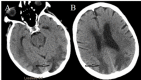

Although a neurological examination is fundamental to the evaluation of comatose patients, it is less reliable in a medically induced coma. A commonly misinterpreted finding in patients in a pentobarbital coma is altered pupillary reactivity secondary to an exaggerated ciliospinal reflex. Recognizing an exaggerated ciliospinal reflex in patients in a pentobarbital coma is important and may prevent unnecessary intervention. We present a patient induced in a pentobarbital coma for the treatment of status epilepticus who exhibited a nonreactive pupil secondary to an exaggerated ciliospinal reflex confirmed by pupillometry. We also discuss the anatomy of the ciliospinal reflex and literature regarding its clinical relevance.